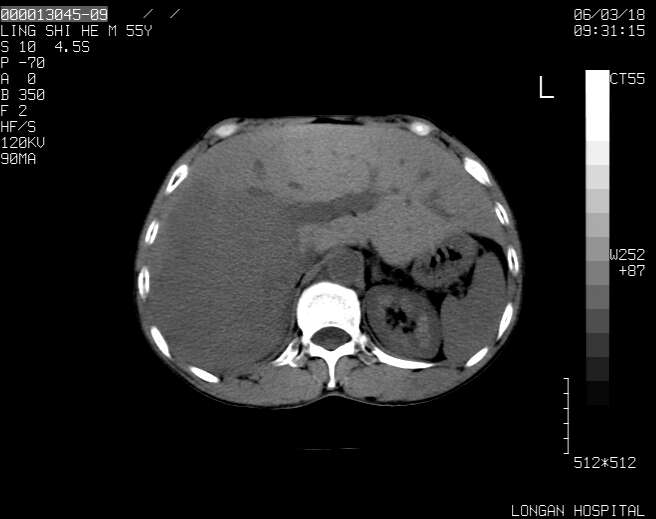

以下是引用guzhongliangddd在2006-3-21 22:13:00的发言:[br]病灶主要位于肝右叶的后份,内见异常血管,门脉主干及右支受侵{提示有癌栓形成},门腔间隙内见增大淋巴结。肝左叶内未见异常。

以下是引用zhuxinli在2006-3-22 1:23:00的发言:[br][br] 病灶主要位于肝右叶的后份,内见异常血管 .门脉右支截断,右叶前段早期强化(考虑动静脉漏),腹膜后肿大淋巴结,病灶逐渐强化,考虑为胆管细胞癌[br]